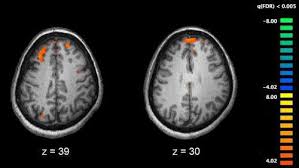

Brain Areas Active During Different Types Of Hallucination In A Patient Download Scientific Diagram

Brain Areas Active During Different Types Of Hallucination In A Patient Download Scientific Diagram from www.researchgate.net